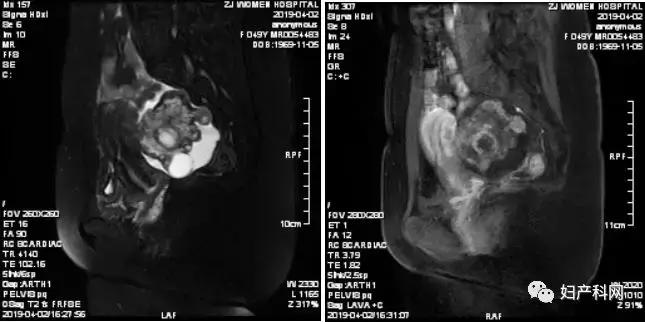

为进一步明确肿瘤来源及性质,入院后行盆腔MRI检查(见图2),结果提示:两侧附件区域占位,首先考虑卵巢恶性肿瘤,转移性可能,建议全腹CT检查。附见:骶椎及两侧髂骨斑片样异常影,转移可能(磁共振MRI可较好的判断肿块性质及其周围器官的关系,有利于病灶定位及病灶与相邻结构关系的确定)。

图2

根据患者病史及盆腔MRI结果,目*考前**虑“转移性卵巢肿瘤”可能性大。患者既往乳癌术后病理提示为浸润性小叶癌,是一种少见的病理类型,约占乳腺癌的10%左右。乳腺浸润性小叶癌术后的复发具有一定特征性,一旦出现转移,往往呈多部位转移,且常见部位为骨,胃肠道,腹膜及卵巢。该患者既往乳腺癌术后分期PT1N3M0,IIIC期,淋巴转移情况严重,临床分级较高,本身存在高复发转移风险。入院盆腔MRI提示考虑存在骨转移及卵巢转移可能。综合上述情况,目*考前**虑乳腺癌转移至卵巢可能性大。